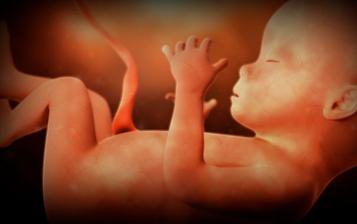

23.5. pro průkazku + odběr krve + utz 11+0 mimisek 4,2cm